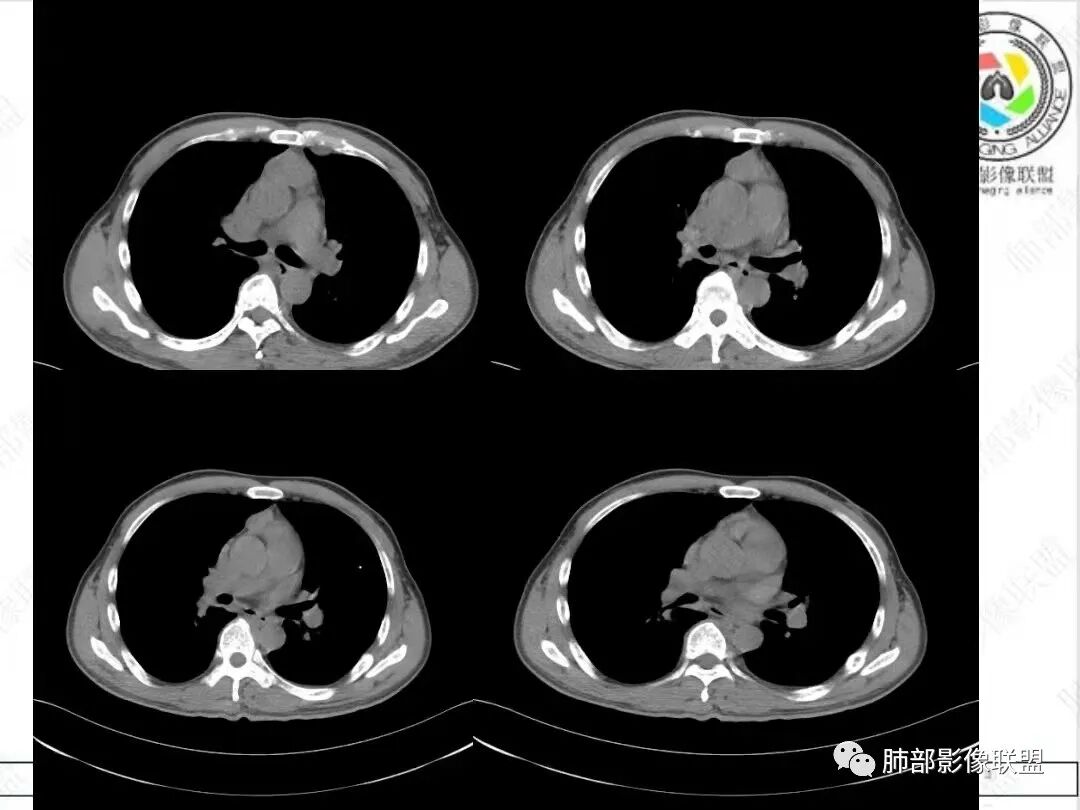

2、影像特点:胸部CT:平扫,前纵隔肿物,基本居中,与周围结构局部分界不清。增强后显示轻中度强化。肿块沿血管间隙侵袭性生长,左无名静脉受压明显变形受侵。纵隔、右肺门多处大小不等淋巴结,左侧内乳淋巴结稍增大。右侧瘤肺交界面光滑,左侧凹陷,肺组织未见明显受侵。右肺中下叶可疑小结节。胸椎及肋骨骨质增生性破坏。肋骨骨折。

很多老师提到前纵隔占位+血管肿块内漂浮+内乳淋巴结增大+轻中度强化=淋巴瘤,淋巴瘤确有上述特点,但本例血管漂浮不明确,病灶强化不均匀,胸椎及肋骨可疑增生性转移,应想到胸腺癌或不典型类癌的可能性。